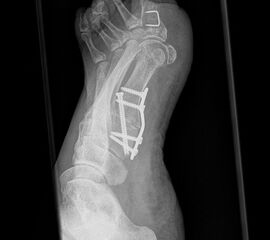

Besondere Bemerkungen zum Beispielbild:

• Valgusarthrose des Sprunggelenks.

• Diskret varische Beinachse bei medial betonter Arthrose des Kniegelenks.

• Lateral des OSG ist eine Eichkugel eingeblendet, die als Referenz bei der Planung von Endoprothesen dient.

• Verkalkung medial in den Weichteilen des Unterschenkels.